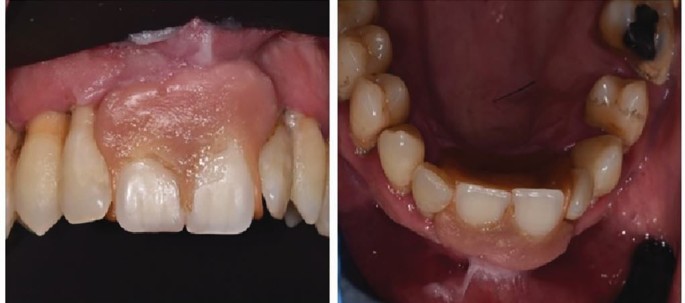

Fear not Finlay Sutton your job is safe. While commendable for its innovation, the homemade partial acrylic denture revealed some failings in support, stability, and retention (Fig. 2) and its design was inherently unhygienic, contributing to inflammation of the soft tissues surrounding the denture-bearing area. Further clinical examination revealed inflamed gingivae and the presence of multiple carious lesions, underscoring the patient's unmet primary dental care needs.